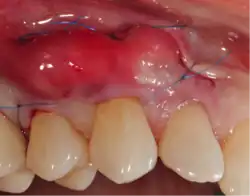

A small amount of blood (10 millilitres (0.35 imp fl oz; 0.34 US fl oz) per tube) is harvested and spun in a centrifuge for eight minutes at 1300 RPM. A fibrin clot packed with blood-derived growth factors, extra cellular matrix and hematopoietic stem cells is fabricated and implanted into the gums above the area of gum recession. Advanced platelet-rich fibrin will promote the patient's own gums to fabricate more gum thus eliminating the need to harvest gums from the roof of the mouth or the use of allografting tissue.

Traditional gum grafting will have a piece of the gums harvested from the roof of the mouth and sutured facing the exposed root to increase the lost keratinized tissue.[11] The limitation in quantity and the morbidity are the limiting factor of this technique. Allografting techniques (skin from cadavers bought from tissue banks) are used as well to supply the surgeon with larger amount of tissues when needed in larger cases,[12] but the type of healing and the risk of possible disease transmission should be considered and disclosed to the patient when opting for such technique.[13]